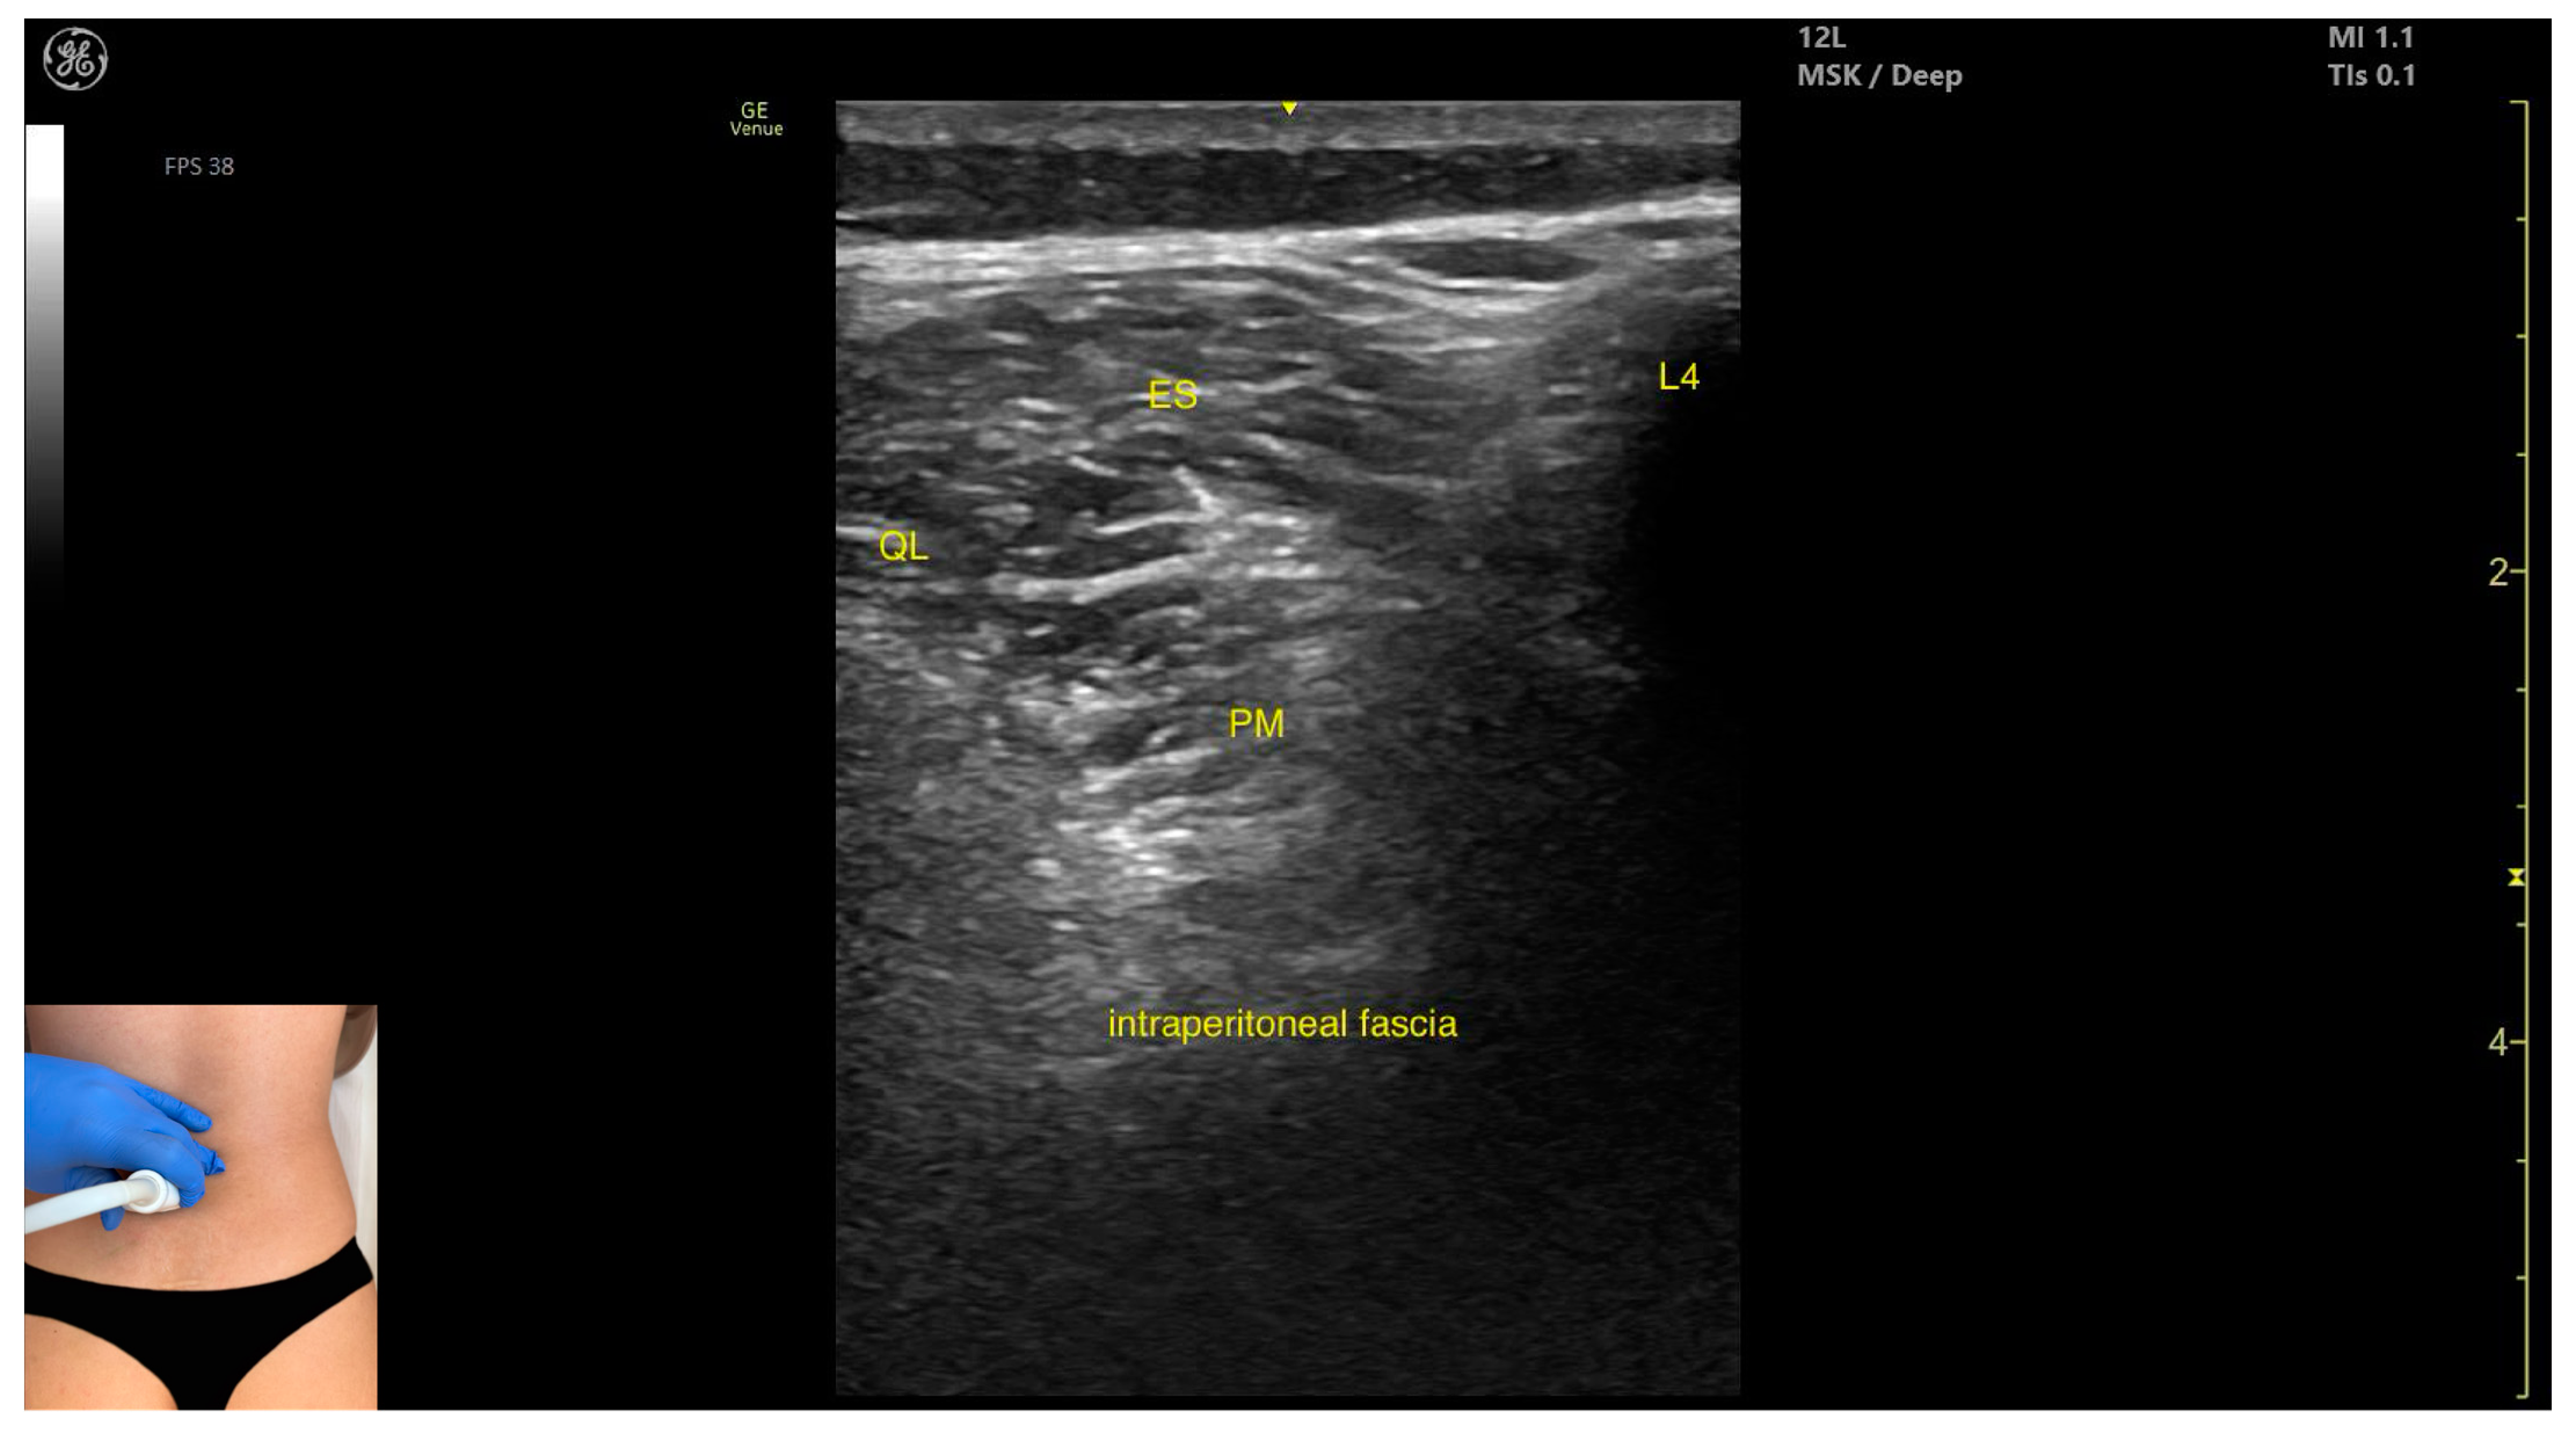

3.3. Psoas Major

3.3.2. Ultrasound Identification

3.3.3. Key Ultrasound Landmarks

- Muscle position: It is the deepest muscle mass at this level.

- External fascia: It presents a pronounced fascia that separates it from the erector spinae and quadratus lumborum, aiding in safe botulinum toxin injection.

- Dynamic evaluation: During dynamic evaluation, when scanning proximo-medially toward the costal arch, its origin is visualized from the T12 to L5 vertebrae.

- Contraction is visible during hip flexion, as well as lumbar spine flexion and lateral inflection maneuvers.

- The psoas major can also be visualized using a longitudinal transducer position, placed superior to the iliac crest and 2 cm lateral to the L4 spinous process. In this view, both the psoas major and the overlying quadratus lumborum are seen superficial to the intraperitoneal space.